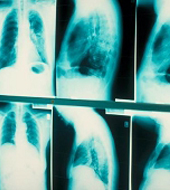

为了正确诊断你是否患上肺癌,医生可能会进行各种检验,包括X光、验血及进行手术抽取肺液或组织样本进行化验。